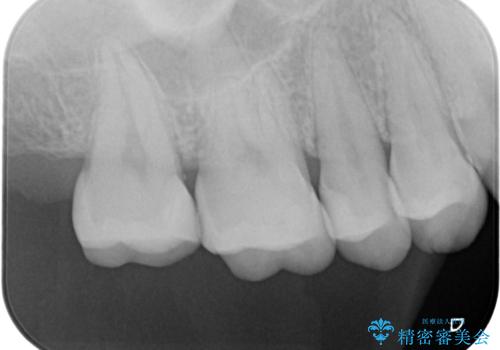

歯と歯の間の虫歯の治療。(コンタクトカリエス)

- メンテナンスで歯と歯の間に虫歯があったので拡大鏡下で虫歯を全て取り除き、e-maxインレーにて治療を行いました。

- e-maxインレー 7.7万費用は治療当時の料金となります